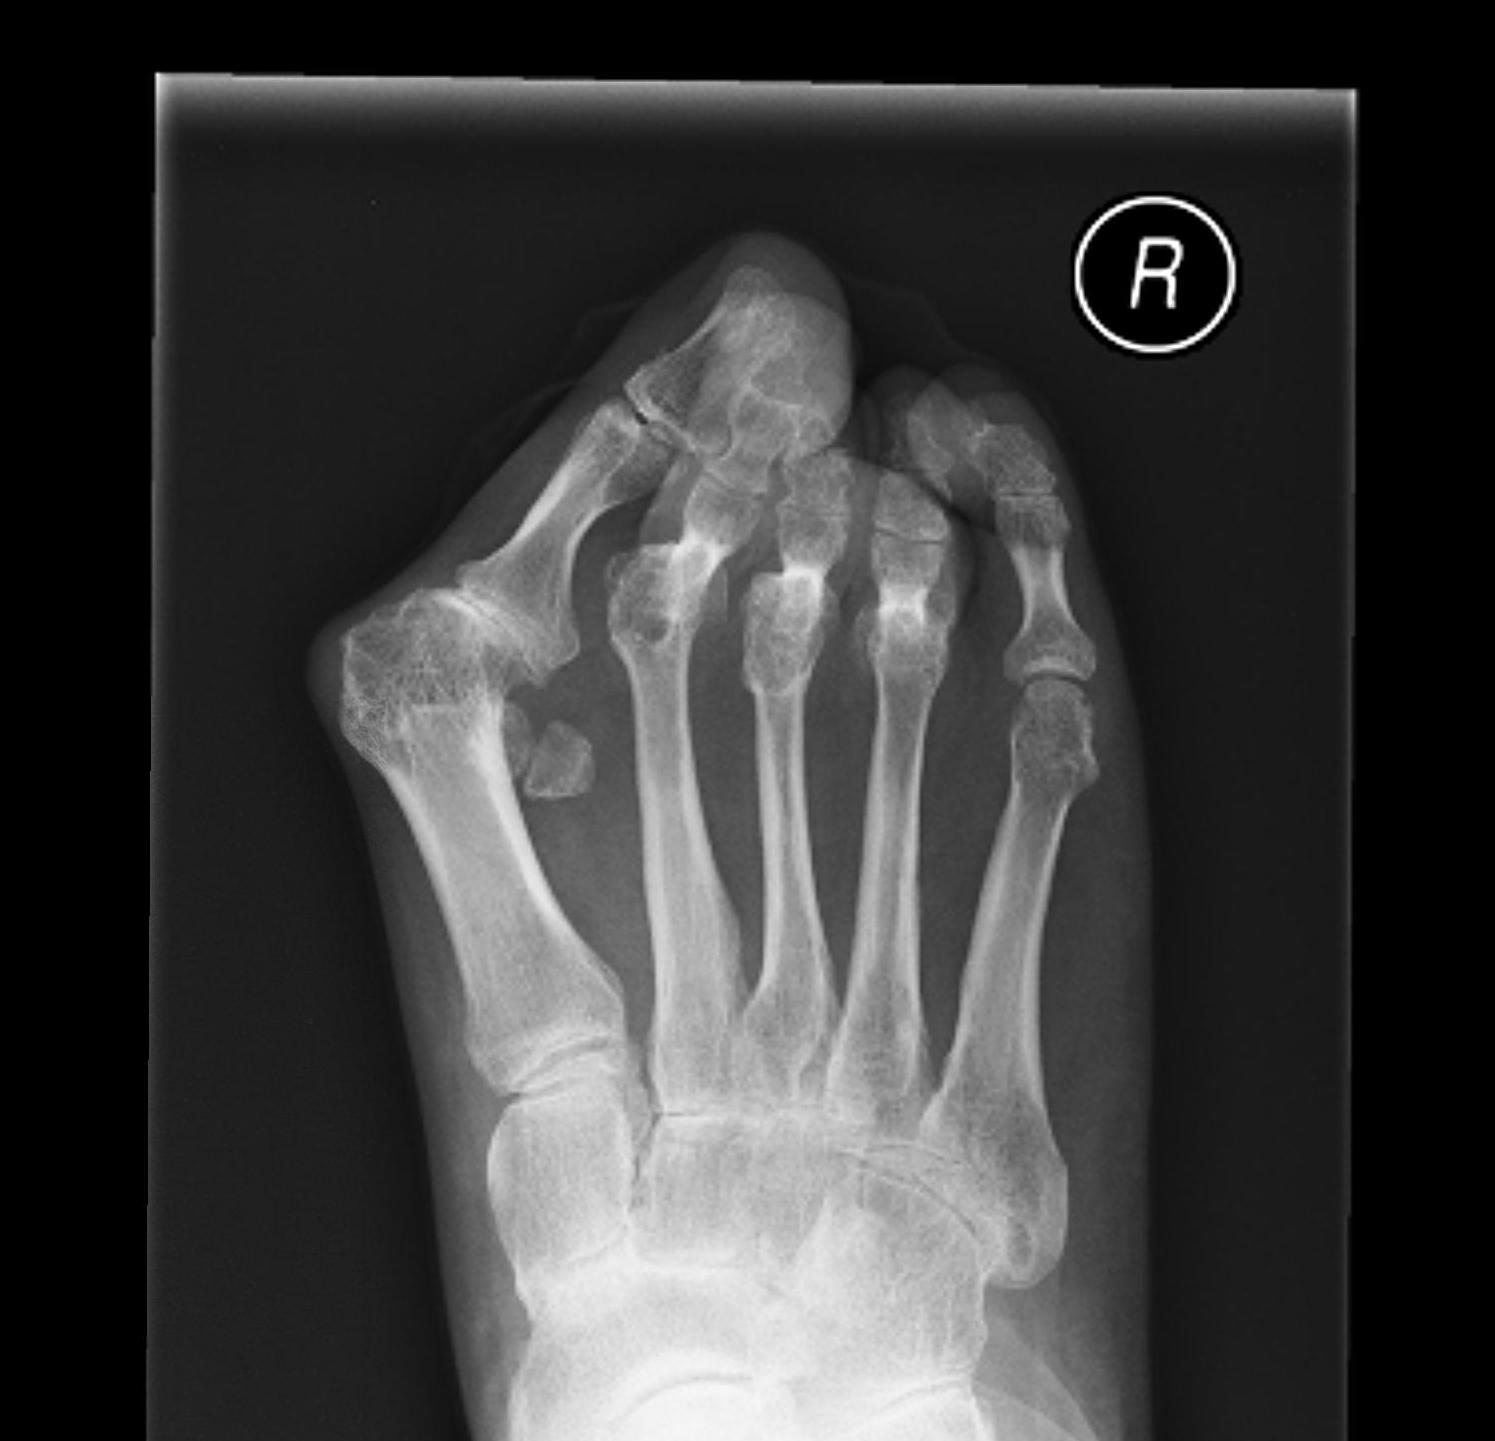

Muller-Weiss disease

Definition

Spontaneous osteonecrosis of the navicular